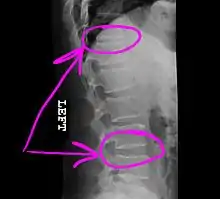

Example of how a telestrator might annotate a medical image shared during a telemedicine session.

Today, the telestrator is used in a wide variety of applications (from educational, boardroom, church and military presentations to telemedicine conferences), where it can be used by both the near and far ends to annotate precise details of microscopic images or other medical images that are under consultation. The telestrator is also used in courtrooms to communicate details of multimedia images presented to a jury, as was most famously seen during the O. J. Simpson trial in March 1995.[2]